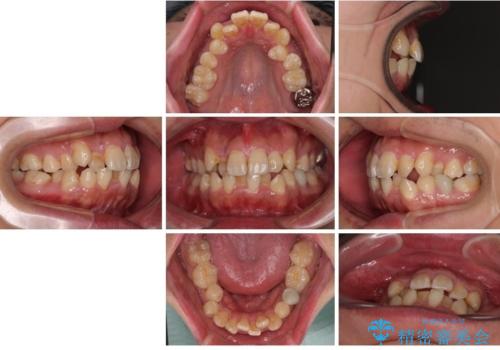

前歯のデコボコを抜歯矯正で改善した症例|目立ちにくい審美装置を使用

- 「歯並び全体のデコボコをきれいに整えたい」とのご希望で、20代男性の患者様が来院されました。

特に前歯部の叢生(歯の重なり)が強く、見た目だけでなく歯磨きのしにくさも気にされていました。

診査の結果、上下前歯に強い叢生が認められ、歯をきれいに並べるためのスペースが明らかに不足していました。

無理に歯を並べると、前歯が前方に突出するため、抜歯によるスペース確保が必要と判断しました。

上下左右の小臼歯を抜歯し、歯列を整えるためのスペースを確保

左下は第二小臼歯に根管治療歴があったため、左下のみ第二小臼歯を抜歯しアンカースクリューを併用

それ以外の部位は第一小臼歯を抜歯

矯正中の見た目を気にされていたため、プラスチックブラケット+コーティングワイヤーを使用した、目立ちにくい審美矯正装置を選択しました。